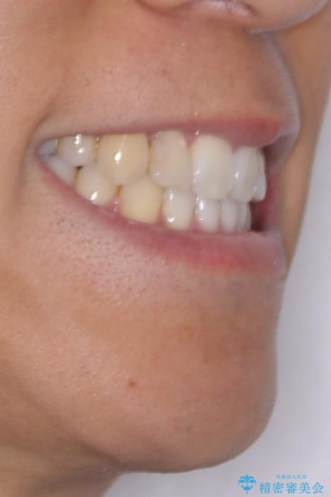

八重歯と前歯のガタガタを抜歯矯正で治療|クリアブラケット使用例

- 「八重歯を治したい」とご相談いただいた患者様の症例をご紹介します。

上下の前歯部に強い叢生(ガタガタの歯並び)があり、そのまま歯を並べると出っ歯になってしまう可能性がありました。

そこで、上下左右の第一小臼歯を抜歯し、歯が並ぶためのスペースを確保し叢生を解消する治療計画を立てました。

矯正装置は、審美性と費用面のバランスを考慮して、プラスチックブラケットとメタルワイヤーを使用しました。

透明感のあるブラケットを用いたため、従来の金属装置よりも目立ちにくく、日常生活での見た目の不安も軽減できます。

八重歯はきれいに整い、前歯もバランスよく収まり、横顔のラインも自然に改善されました。

治療後、患者様は「思い切り笑えるようになった」と大変喜んでくださいました。